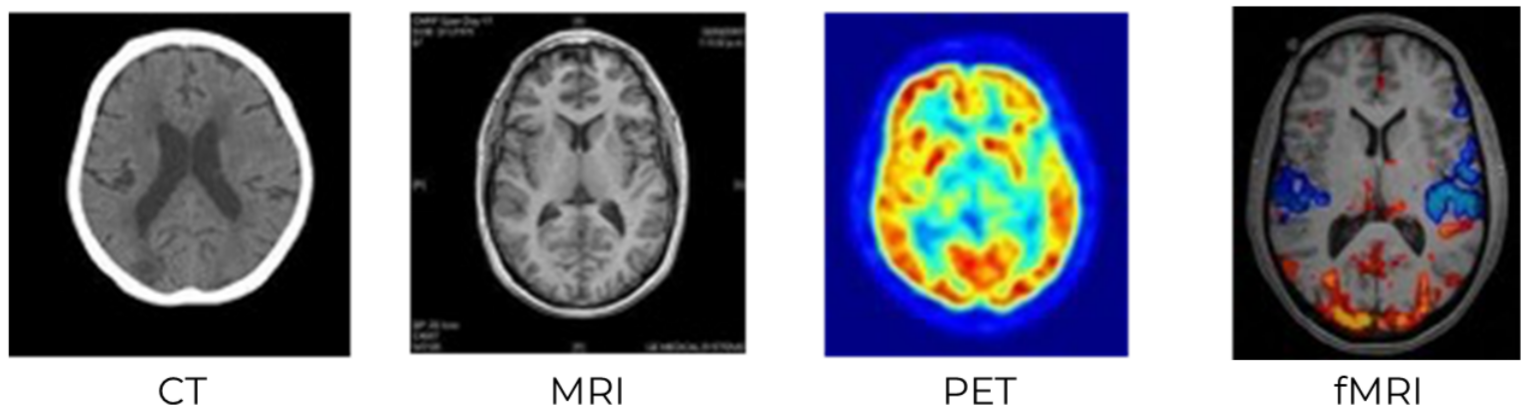

Brain Imaging Techniques (MRI, fMRI, PET, CT)

Doctors use several non-invasive scans to study the brain. These techniques help reveal both structure and function, making diagnosis and research safer and clearer.

🌟 1. MRI (Magnetic Resonance Imaging)

- A scan using strong magnetic fields and radio waves to create high-resolution images of brain structure.

🌟 2. fMRI (Functional MRI)

- A type of MRI that tracks brain activity by monitoring blood oxygen levels.

🌟 3. PET (Positron Emission Tomography)

- A scan that uses radioactive tracers, usually glucose labelled with a positron emitter, to show metabolic activity.

🌟 4. CT (Computed Tomography)

- An imaging method using X-rays from many angles to create cross-sectional brain slices.